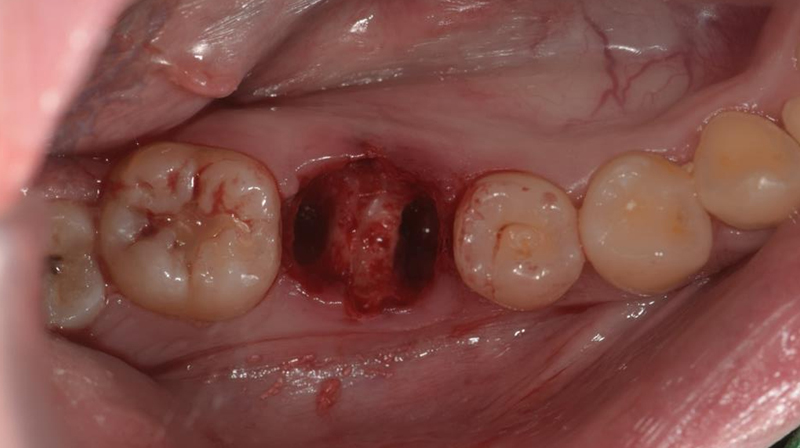

拔除右下第一大臼齒

拔除智齒,固定至第一大臼齒缺牙區域

術前